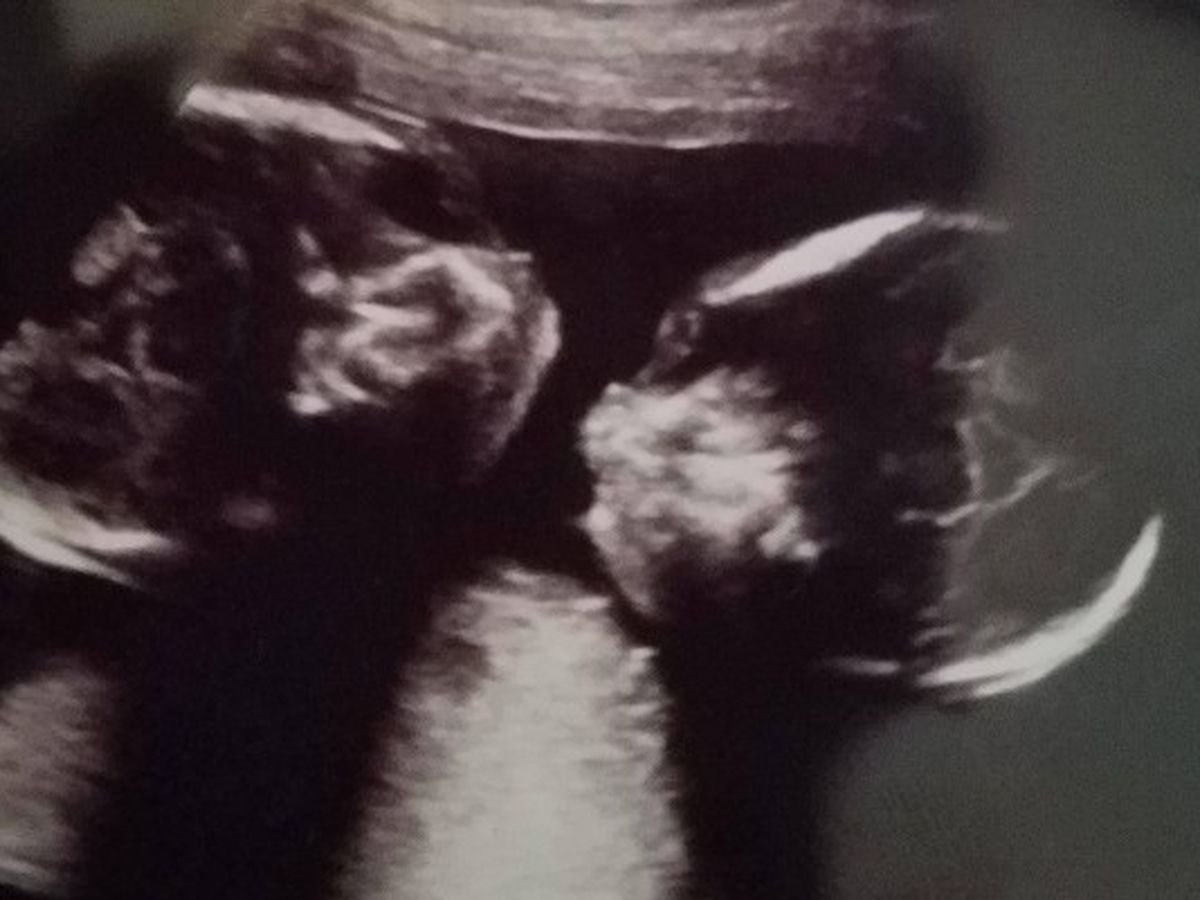

Hello my name is Fuschia and my husband and I found out we are having conjoined twin girls! We found out at my 20 week ultrasound check up. When I found out I was pregnant I had to know the gender. When my OB/GYN ran labs we found out we were having a girl. I was beyond excited because we have a little boy already. Fast forward to my 20 week ultrasound. I was exploding just to see our daughter. As the ultrasound ensues my Dr begins scanning I see her head. Not blinking I continue to stare I see another head....Wait I felt like I miss saw I blurt out is that a second baby? He's quite as he continues to go back and forth. I look at my husband as the Dr. continues he goes to get my midwife. They both begin to inform us there are indeed two babies, twins but there conjoined and sharing organs. Feeling like all the air had been sucked out of the room I cry. What did I do to my girls? How? Why? I was told its nothing anyone did its just a random occurrence that happens 1 in every 200,000 births. My care was then transferred to a high risk Dr.

The closets MFM was about 3 hours away. In the beginning we were having weekly appointments. The MFM appointments were very informative yet disappointing as they confirmed the girls were indeed sharing a heart and liver. Aborting became the new topic when meeting new doctors. We knew that wasn't an option for us. We were told the girls chance of survival to birth were slim and if they did make it to birth there was only a 50% chance they'll survive the first 24 hrs. Again no good information. I couldn't believe because I feel them moving around all the time just like with my son very active. My family and friends pray and we have faith that the girls will have a long life whether it be together or separate. Our family had to relocate because of all expenses accruing and better healthcare for our babies. We relocated to NJ our son has been so good with all the travel and doctors appointments. sense moving all the appointments are going well. The girls are growing just fine and continue to be very active. Our son is very excited about his sisters coming. Our family continues to await our precious girls with excitement and anticipation. Thank you for reading and contributing if you feel the need or want to do so. WELCOME to Lailani and Iyana's Journey!! The girls also have a FB page if you wish to follow for frequent updates. https://m.facebook.com/Lailani-Iyanas-Journey-182941592303462/?ref=bookmarks